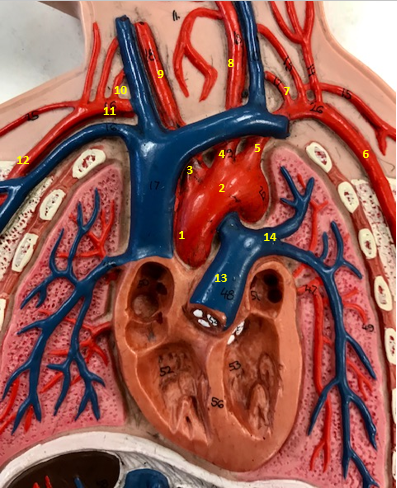

Aorta

Name #2

Brings blood out of left ventricle

Function of aorta

Brachiocephalic artery

Name #3

Supplies oxygenated blood to right arm shoulder neck and head

Function of brachiocephalic artery

Left common carotid artery

Name #4

Supplies oxygenated blood to left neck and head

Function of left common carotid artery

Left subclavian artery

Name #5

Supplies oxygenated blood to left arm shoulder

Function of left subclavian artery

Left axillery artery

Name #6

supplies blood to left armpit and upper limb

Function left axillary artery (6)

Left vertebral artery

Name #7

Supplies blood to brain and spinal cord

Function of left vertebral artery (7)

Left common carotid artery

Name #8

Supplies blood to left neck and head

Function of left common carotid artery (8)

Right common carotid artery

Name #9

Supplies oxygenated blood to right neck and head

Function of right common carotid artery (9)

Right vertebral artery

Name #10

Supplies blood to brain and spinal cord

Function of right vertebral artery (10)

Right subclavian artery

Name #11

Supplies blood to right arm and shoulder

Function of right subclavian artery

Right axillery artery

Name #12

Supplies blood to right armpit and upper limb

Function of right axillery artery (12)

Pulmonary trunk

Name #13

Bring blood out of right ventricle to lungs

Function of pulmonary trunk (13)

Left pulmonary artery

Name #14

Bring blood to left lung

Function of left pulmonary artery (14)